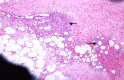

BACKGROUND Myelolipoma is a benign tumor, commonly found in the supra-renal gland, which is composed of mature fatty tissue admixed with hematopoietic elements. However, there are several extra-adrenal sites reported in the literature and thoracic myelolipoma is an unusual location for extra-adrenal myelolipoma. CASE REPORT We present the case of a 71-year-old man previously diagnosed with hypertension who was admitted due to a motor vehicle injury with a lumbar spine fracture. The patient developed non-ST segment elevation myocardial infarction during admission. A coronary angiogram revealed three-vessel disease. Triple coronary artery bypass grafting (CABG) surgery was planned. Upon opening the chest through median sternotomy, a retrosternal adherent mass was incidentally discovered. The mass was excised and histopathological evaluation showed it was myelolipoma in the anterior part of the mediastinum. CONCLUSIONS It is well known that myelolipoma occurs in extra-adrenal sites, and is rarely found at unexpected site, as in our case, which was found incidentally at the anterior mediastinum. With an extensive literature review, we found only 1 case located in the anterior mediastinum. It is crucial to know that myelolipoma can occur in the anterior mediastinum to avoid pitfalls with other differential diagnoses, especially when it is found incidentally and requires a frozen section examination, as it is difficult to diagnose through radiologic imaging only because it can overlap with tumors that are rich in either adipose tissue or hematopoietic elements. However, it affects patient management, and patients usually need only follow-up instead of going through invasive procedures for resection of non-functional tumors, especially in older patients or patients with comorbid diseases.